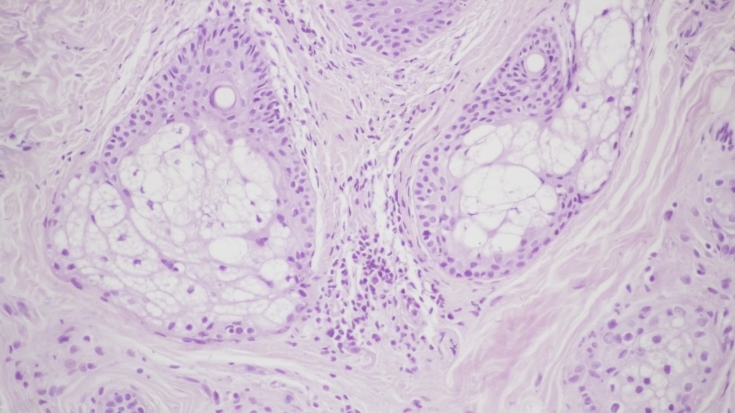

Малий. 3. Морфологічна картина шкіри перед проведенням лікувальних заходів: виражена вогнищева запальна інфільтрація дермі, х200; запальна інфільтрація навколо волосяних фолікулів, ознаки фіброзу, х200; проліферація дрібних сосудів капілярного типу з периваскулярною лімфоїдно-клітинною інфільтрацією, х200;

мал.4. Ізолований радіохвильовий вплив на шкіру. Збереження запальних елементів на фоні зниження лімфоїдно-клітинної інфільтрації дерми при огнищевій проліферації фібробластів, х200.